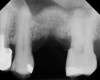

A 74-year-old male patient presented with about 4 mm to 5 mm of native bone in the No. 4 position (Figure 17). A composite graft, as described in Case 1, was used, as was the same implant type, but the implant was 11.5 mm in length with a taper of 5 mm to 4.2 mm. The approximately 16-month post-healed floor of the sinus was raised about 7 mm to 8 mm (Figure 18). The CBCT scan taken at 16 months postoperatively showed no change in appearance from the area of the old floor of the sinus to the new bone formed (Figure 19). Although it was endodontically involved, tooth No. 15 was not extracted, against professional advice. As can be seen in Figure 18, the No. 14 implant is acting as a bridge abutment.

This patient was a 73-year-old man with only about 3.5 mm of native bone in the No. 3 site (Figure 20). The composite graft used here was a 50:50 mixture of DFDBA and deproteinized bovine bone mineral (Osteohealth, www.osteohealth.com) with approximately 40% calcium sulfate added. The implant was the same type and length as in Case 1 above. Figure 21 shows the area on the day of placement. In the CBCT scan on the day of placement (Figure 22), the native bone and bone graft were clearly discernable. However, the postoperative radiograph taken at 6.5 months (Figure 23) showed no marginal bone loss and a significantly denser appearance than when the graft was place. The membrane was raised about 7 mm to 8 mm. The final radiograph was taken after extraction of tooth No. 2 and after extraction of tooth No. 4 and immediate implant placement.